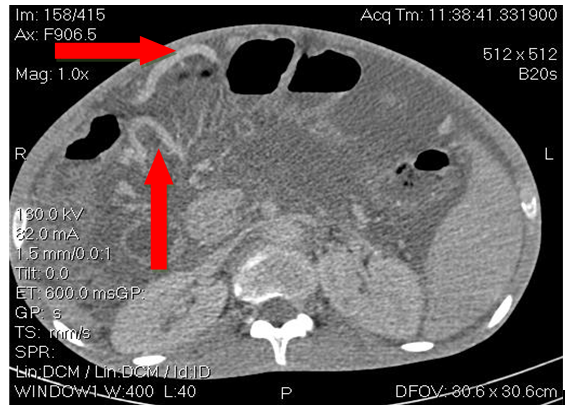

He was a 23-year-old male with no previous history, including no ethylo-smoking or cardiovascular pathology, admitted in November 2018 for diffuse, atrocious, diffuse abdominal pain, sudden twisting associated with vomiting and a cessation of materials and gases. The physical examination revealed an abdominal meteorism. The unprepared abdomen radiograph (ASP) had objectified hydro-aerobic levels wider than high. Acute intestinal obstruction by volvulus of the hail was suspected. He underwent an emergency laparotomy which revealed acute mesenteric ischemia for which an ileal resection of approximately 1.5m with terminal ileo-ileal anastomosis was performed. The postoperative effects were marked by the recurrence of the mesenteric infarction clinical presentation one week later requiring surgical resection with a new 50cm ileum resection and terminal ileo-ileal anastomosis. The evolution was marked by the appearance of an alteration of the general state (performance status index at 2 according to the World Health Organization); with anorexia, significant weight loss, malabsorption diarrhea made of liquid stools, at least 10/day containing food residues; with the occurrence of ascites whose puncture shows a liquid low in protein at 0.59g/l. The patient was then transferred to the gastroenterology department for further assessment. On physical examination the patient had an impaired general condition with a BMI of 16.4Kg/m2. The abdomen was enlarged (Figure 1) with signs of portal hypertension (collateral venous circulation, splenomegaly and ascites). Biologically, he had hepatocellular insufficiency (low prothrombin (TP) rate at 49.2%, low albuminemia at 30.7g/l). The electrophoresis of the proteins objectified a biological inflammation syndrome (hypoalbuminemia at 30.7g/l and hypergammaglobulinemia at 37g/l). Esophageal endoscopy noted the presence of grade II esophageal varix without red sign with intense portal hypertension gastropathy. Abdominal CT scans (Figures 2A–C) showed atrophic liver, ascites, splenomegaly and intra-abdominal collateral venous circulation. Viral serologies B (HBsAg and total anti HBc antibodies) and C as well as human immunodeficiency virus (HIV) were negative. Lipid and blood sugar levels were normal. The cardiological consultation with electrocardiogram and cardiac ultrasound did not reveal any pathology. A thrombophilia check-up (antithrombin deficiency, protein C and S deficiency, Antiphospholipid antibody, factor V Leiden mutation, prothrombin gene mutation) was requested remotely from the ischemic episode, but not yet performed due to a lack of resources. Symptomatic treatment with analgesics (non-opioid and opioids), evacuation of ascites with diuretics, prevention of rupture of esophageal varices by beta-blocker, slowing of transit (loperamide) and nutritional assistance with oral dietary supplements and iron and calcium supplementation have been instituted. The evolution under this treatment was favourable. The patient was discharged with regular follow-up for screening for hepatocellular carcinoma.

Figure 2C Abdominal CT showing collateral venous circulation.